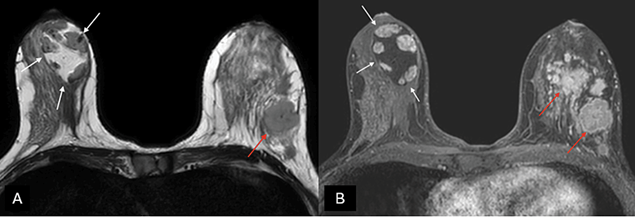

MRI can be useful in establishing a diagnosis if suspicious features are noted on mammography or ultrasound [27]. Otherwise, MRI is not generally indicated for typical MH. On T1- and T2-weighted sequences (Figure 4), hamartomas appear as heterogeneously intense masses with glandular and fatty tissue components and a thin capsule [24]. Once the contrast media has been administered, MH exhibits a gradual, progressive enhancement with a type I time/intensity curve [28].

Figure 4. (A) Axial T2-weighted images and (B) T1-weighted fat-suppressed enhanced magnetic resonance imaging (MRI) – a capsulated, large-sized hamartoma can be seen located in the outer quadrants of the right breast, exhibiting a signal identical to normal mammary gland tissue, creating a “breast within a breast” appearance (white arrows). There are multiple masses in the contralateral breast with suspicious morphology, associated with a known invasive ductal carcinoma (red arrows). Image credits: El Yousfi Z, El Mansoury FZ, El Bakkari A, Omor Y, Latib R. Breast hamartoma with synchronous contralateral breast cancer: a case report. Cureus 2024; 16(8): e66534. DOI: 10.7759/cureus.66534. Reused under the terms of the Creative Commons Attribution License CC-BY 4.0. (https://creativecommons.org/licenses/by/4.0/deed.en).